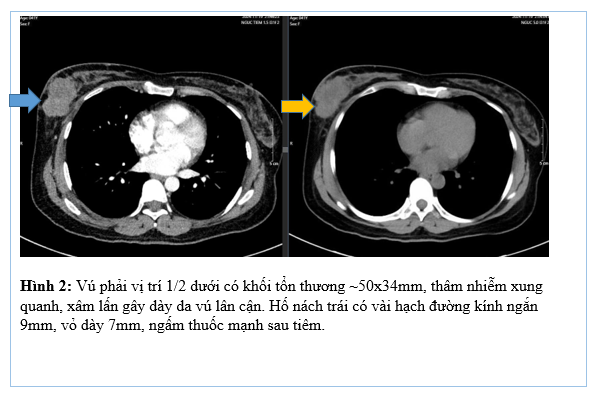

Tháng 01/2025 Bệnh nhân ở nhà xuất hiện mỏi, vàng da, ngứa kèm sốt kéo dài một tháng, đợt này đau bụng mạn sườn phải, kèm vàng da tăng dần, đi khám ở bệnh viện tuyến dưới, siêu âm có sỏi đường mật gan trái kích thước 22×41 mm. Bệnh nhân được chuyển đến bệnh viện Bạch Mai và được chụp CT ổ bụng phát hiện, kết quả: Gan có kích thước bình thường, bờ đều, nhu mô hạ phân thuỳ IV có ổ tổn thương dạng dịch kích thước 40x53mm, trong có sỏi lớn đường kính 35mm.

Hình 1. Hình ảnh sỏi đường mật tạo ổ áp xe gan – đường mật gan trái( vòng tròn màu đỏ). Giãn nhẹ đường mật trong gan hai bên. Dày thành nhẹ ngã ba đường mật trên phim chụp cắt lớp vi tính.

Đánh giá tổn thương trên phim chụp cộng hưởng từ: Nhu mô hạ phân thuỳ IV có ổ tổn thương dạng dịch, kích thước 38x52mm, trong có vài sỏi, sỏi lớn nhất kích thước ~27x37mm, có thông với nhánh đường mật gan phải lân cận, ngấm thuốc viền sau tiêm, chèn ép ngã ba đường mật, gây giãn đường mật trong gan hai bên

Hình 2. Hình ảnh giãn khu trú đường mật gan trái, tạo cấu trúc dạng nang và sỏi đường mật bên trong( vòng tròn đỏ), chèn ép kèm giãn đường mật trong gan hai bên trên phim chụp MRI